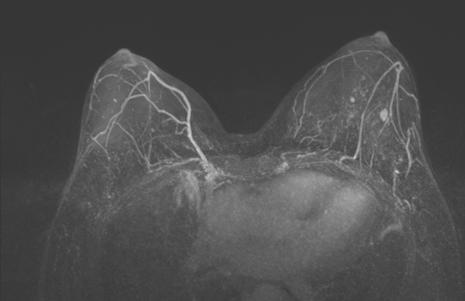

2021-11 乳腺MRI:左乳上份、外上象限见一不规则等T1,等-稍长T2信号肿块,大小约8.2cm×3.7cm×6.5cm,ADC值最低处0.71×10E-3mm2/s,动态增强扫描不均匀显著强化。左腋下多枚肿大淋巴结,大者约2.2cm×1.3cm,增强明显不均匀强化。形状呈不规则,边界欠清楚。

图片

图2. 新辅助治疗前乳腺MRI

图7. 左图为治疗前,右图为治疗6周期后

治疗6个周期后,乳腺增强MRI显示靶病灶明显缩小,临床疗效评估为PR;腋窝靶病灶消失,临床疗效评估为CR。